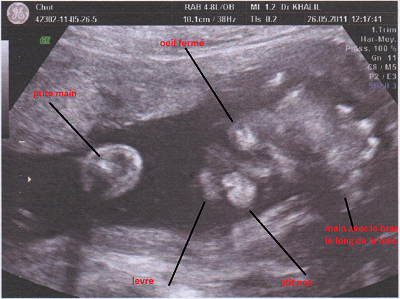

grenouille (CERNAY, 68) répond Posté le 27-05-2011 à 08:40

voila une autre photo commenté pour bien se rendre compte

mais je sais pas sque si on va bien voir sur le forum :-S

alors vite fait on voit un ptit oeil fermé, le nez,la levre sup , et les ptites mains

voila gros bisous